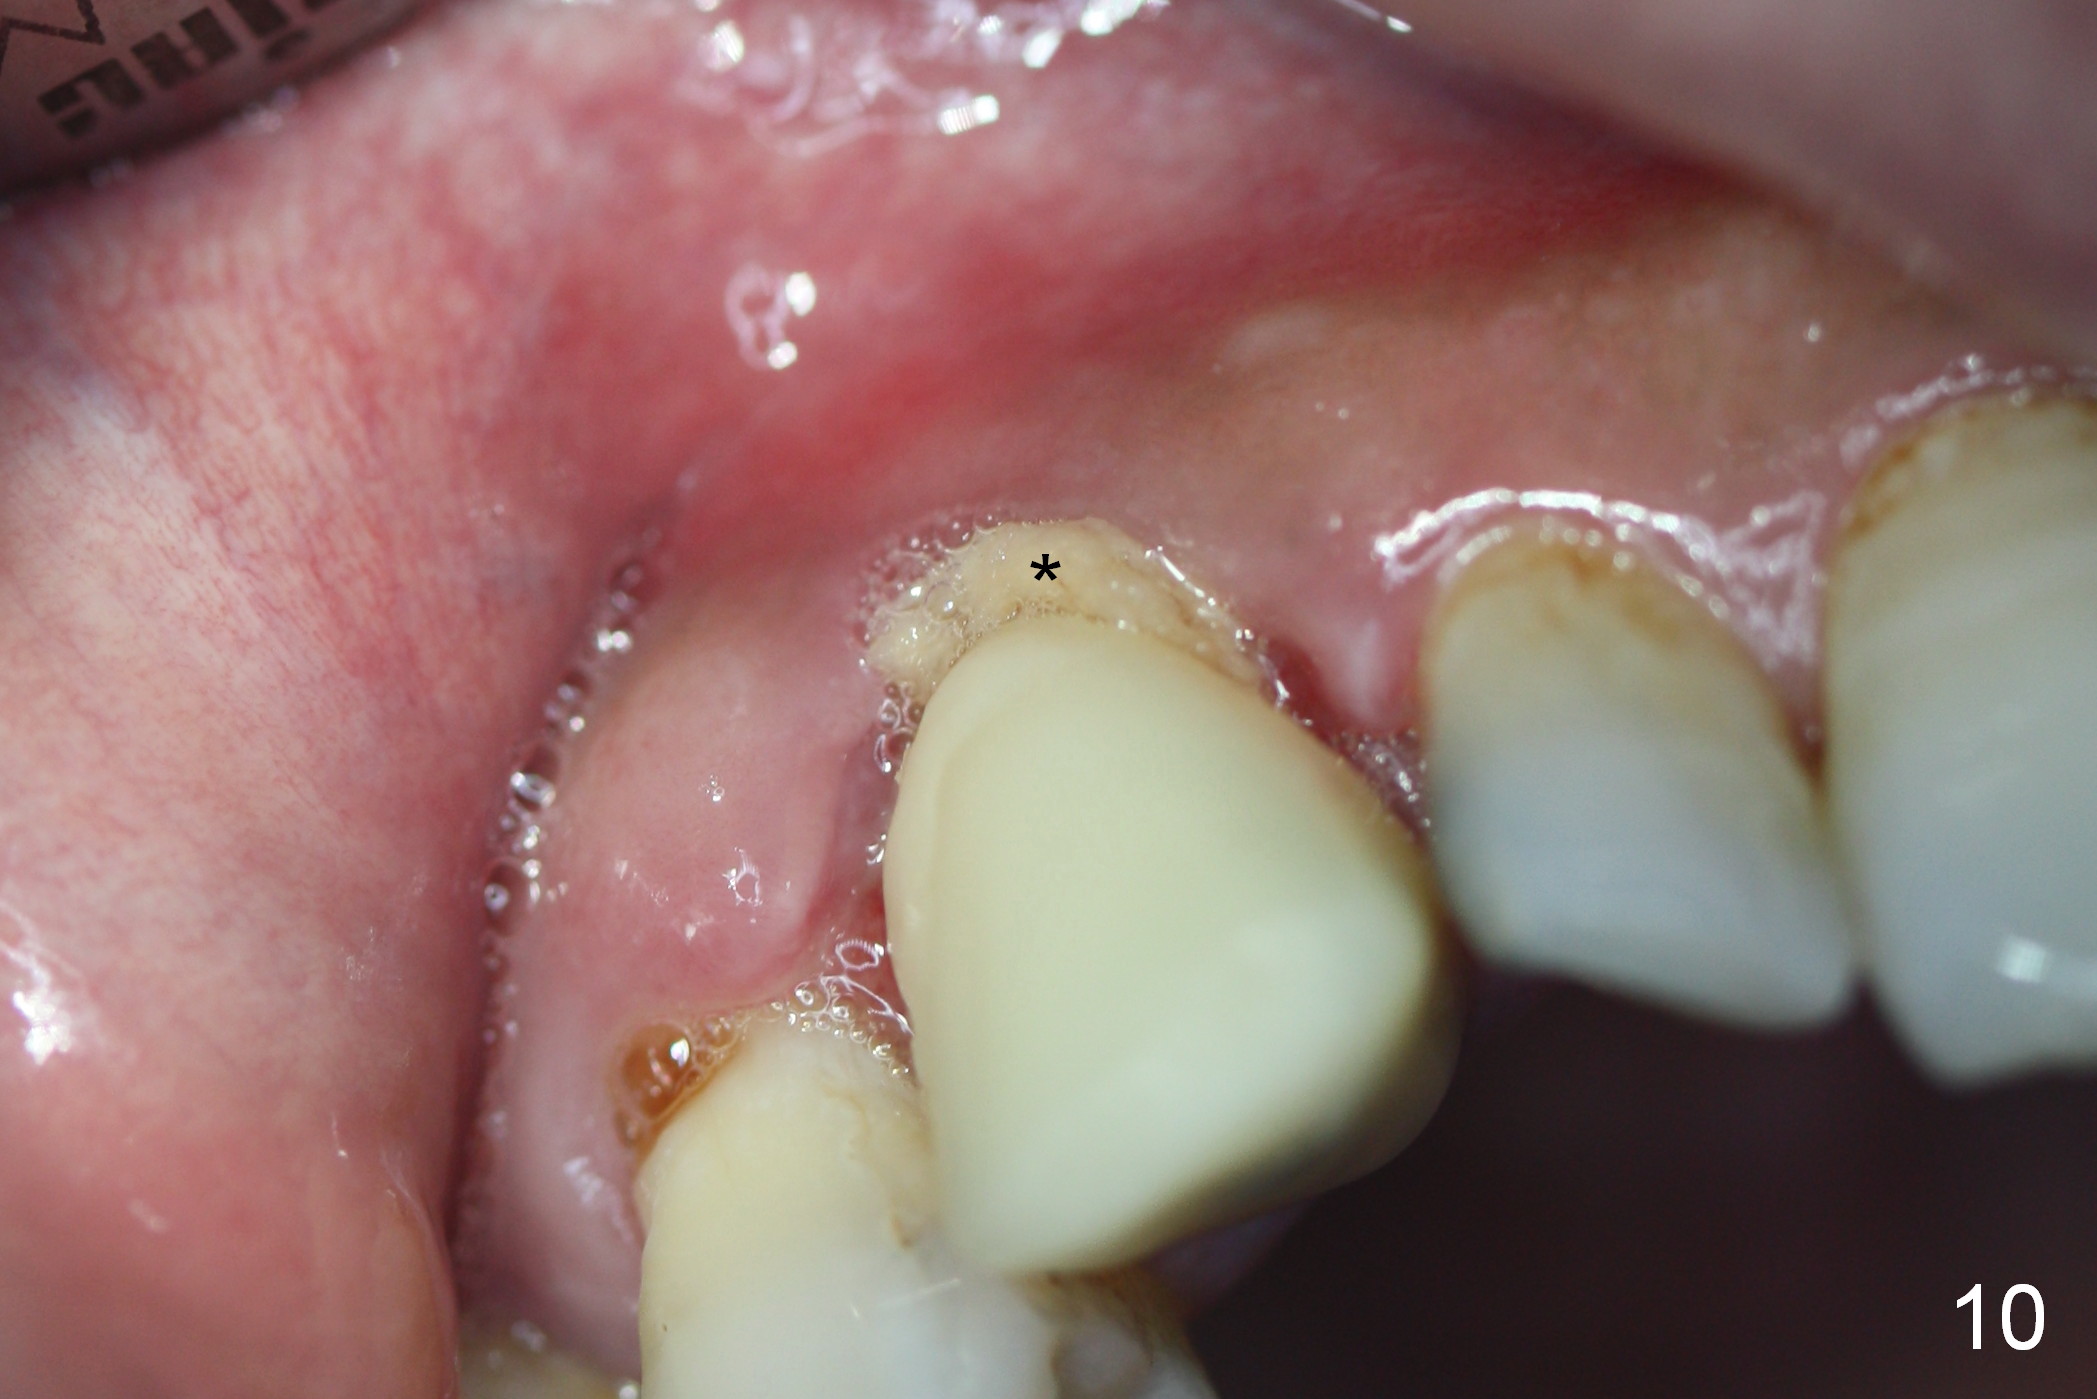

The perio dressing has been dislodged with exposure of the collagen dressing (Fig.10 *) 13 days postop. The graft appears to have consolidated or dislodged since the buccal plate collapses (Fig.11 arrowheads) to the status prior to grafting (as compared to Fig.7).